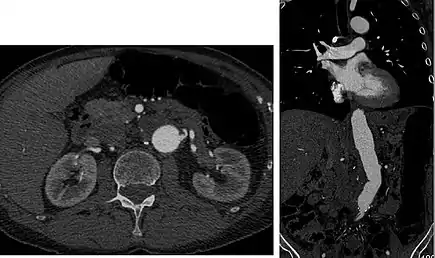

![]() Sagittal thin slice of a computed tomography angiography abdominal aortic aneurysm (AAA) (arrows) | |

Aorta and great arteries

CTA can be used in the chest and abdomen to identify aneurysms in the aorta or other major blood vessels. These areas of weakened blood vessel walls that bulge out can life-threatening if they rupture. CTA is the test of choice when assessing aneurysm before and after endovascular stenting due to the ability to detect calcium within the wall.[2] Another positive of CTA in abdominal aortic aneurysm assessment is it allows for better estimation of blood vessel dilation and can better detect blood clots as compared to standard angiography.[3]